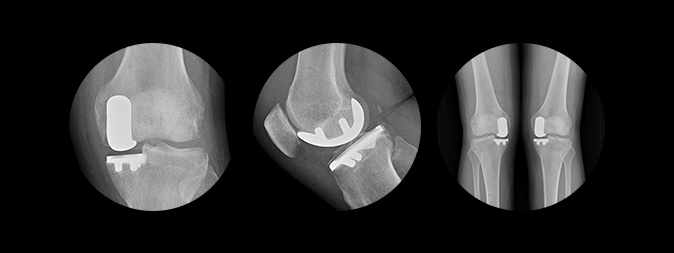

인공관절 부분치환술

수술방법

무릎 관절 중 손상이 심한 부위만 제거하고

정상 연골은 남겨두는 수술

치료대상

무릎관절 중 일부만 손상된 경우(내측관절)